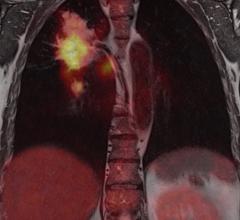

March 15, 2018 – Median Technologies, the industry-leading Imaging Phenomics Company and the Nice University Hospital ...